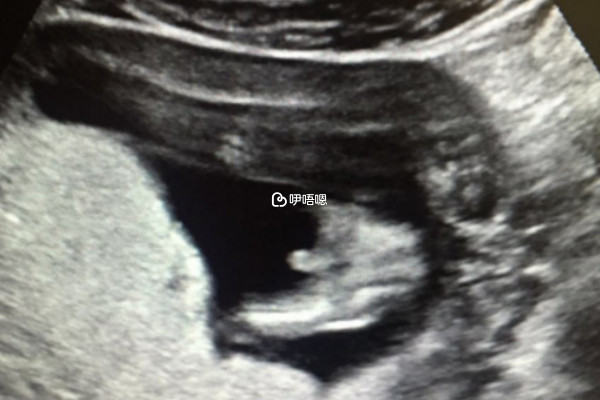

孕6周檢查胎芽4mm胎心微弱一般不會導致胚胎停止發育,由於孕6周懷孕的時間比較短,胎兒的發育還不完全,此時檢查出胎芽4mm胎心微弱是正常現象,各位孕媽也不要過於擔心,可在家休息一週後,再前往醫院進行檢查。若是一週後,胎心還是微弱的話,可以在醫生的指導下進行全面的身體檢查,看是否是其他因素導致,並配合吸氧、服用黃體酮軟膠囊等進行保胎治療,以預防胎停。

由於懷孕後胎心出現是懷孕7-8周,所以6周胎心微弱是正常現象,對於這種情況孕媽可一週後再去醫院觀察胎心情況。而一般導致6周胎心微弱的原因有很多,具體如下: